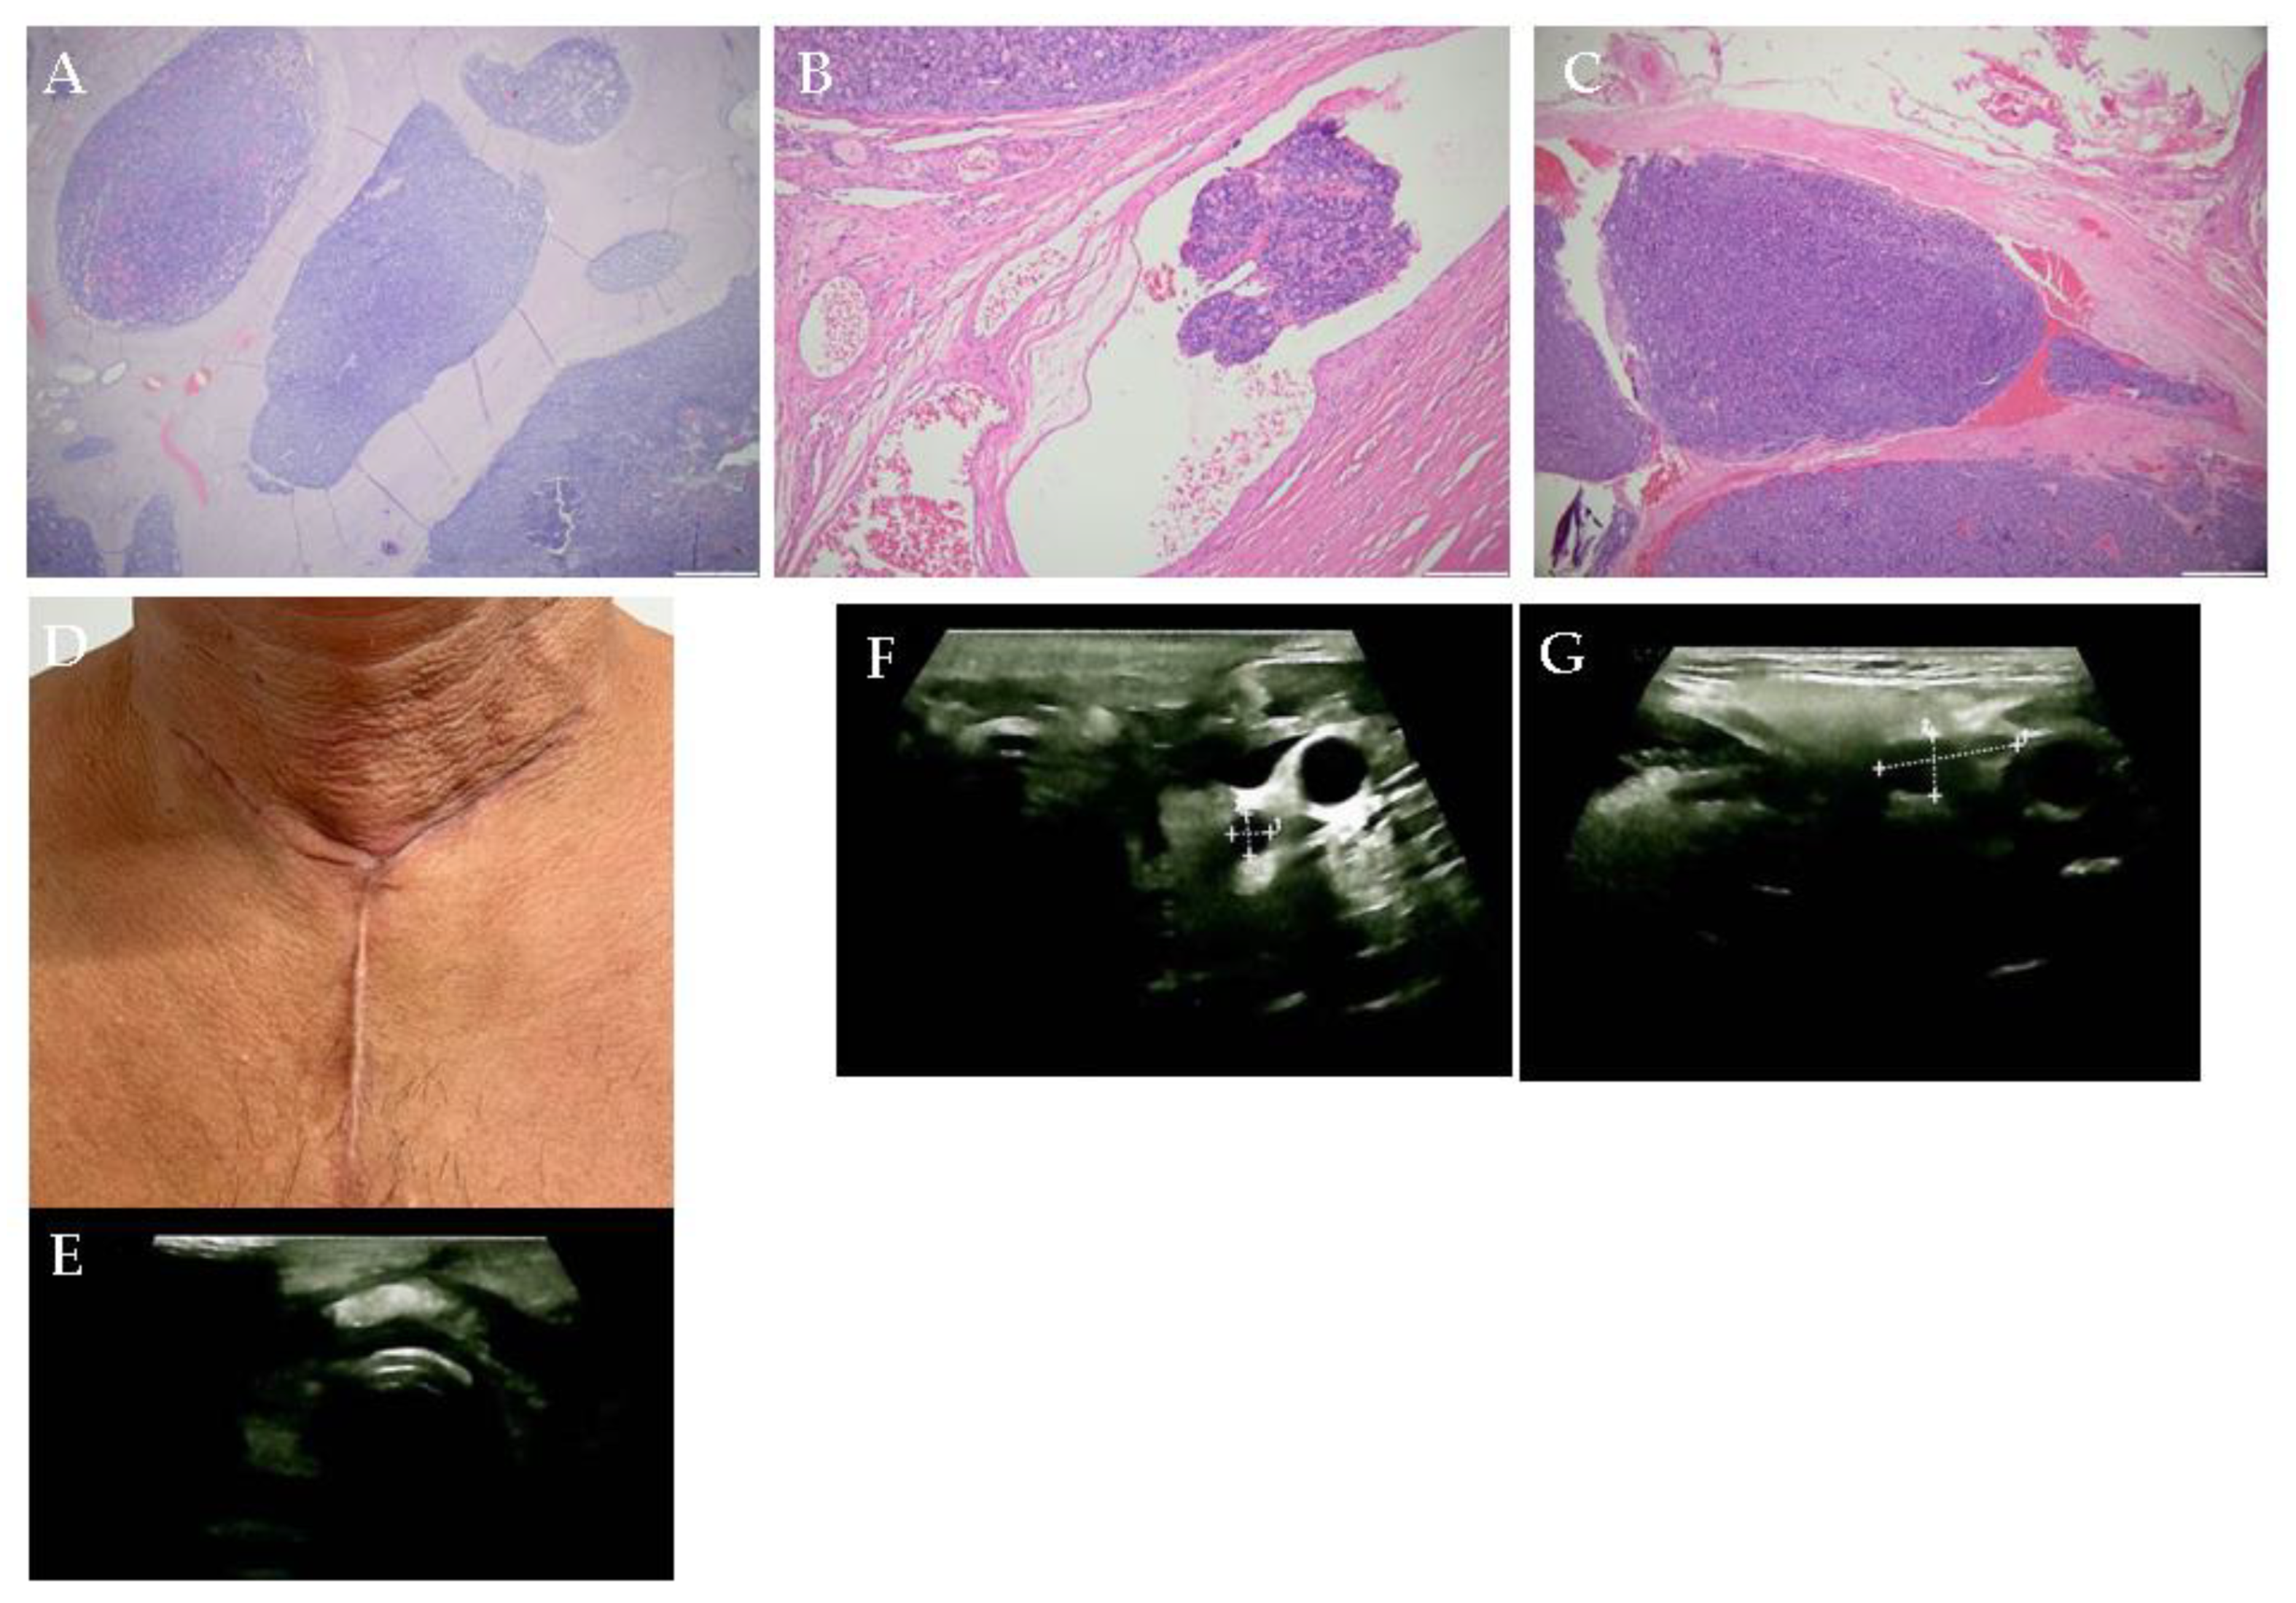

Multilayered Insights into Poorly Differentiated, BRAFV600E-Positive, Thyroid Carcinoma in a Rapidly Developing Goiter with Retrosternal Extension: From En “Y” Cervicotomy to SPECT/CT-Positive Lung Metastases

Sima, O.-C.; Cucu, A.-P.; Terzea, D.; Nistor, C.; Vasilescu, F.; Eftimie, L.-G.; Ciobica, M.-L.; Costachescu, M.; Carsote, M. Multilayered Insights into Poorly Differentiated, BRAFV600E-Positive, Thyroid Carcinoma in a Rapidly Developing Goiter with Retrosternal Extension: From En “Y” Cervicotomy to SPECT/CT-Positive Lung Metastases. Diagnostics 2025, 15, 2049. https://doi.org/10.3390/diagnostics15162049